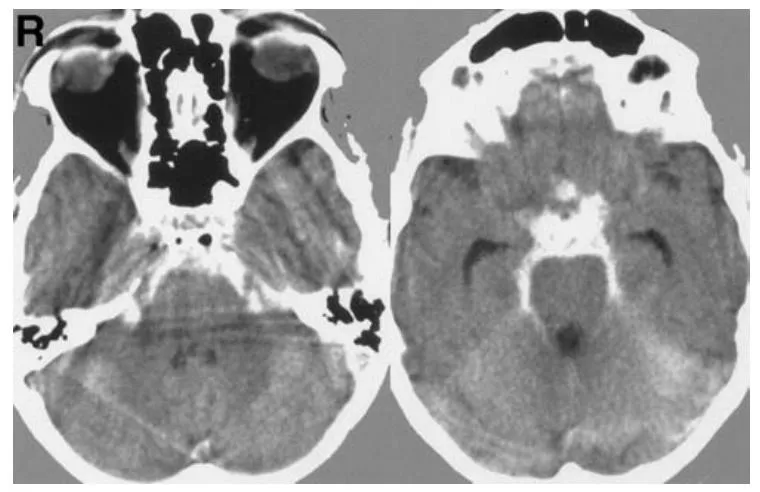

一位57岁男性患者因突发剧烈头痛与恶心症状前往医院就诊。头颅计算机断层扫描检查结果显示存在蛛网膜下腔出血(图1)。该患者既往并无任何神经系统相关症状。

图1 轴位计算机断层扫描图像清晰显示基底池存在蛛网膜下腔出血